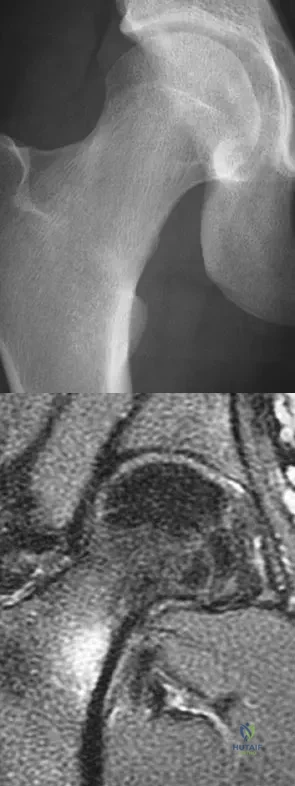

A 25-year-old man has had an insidious onset of left hip pain over the past 11 months. A radiograph, coronal MRI scan, and histopathologic specimens are seen in Figures 2a through 2d. What is the most likely diagnosis?

Explanation

A 42-year-old man reports the recent onset of right hip pain. A radiograph and MRI scan are shown in Figures 38a and 38b. A WBC count, erythrocyte sedimentation rate, and hip aspiration are within normal limits. Management should now consist of

Explanation